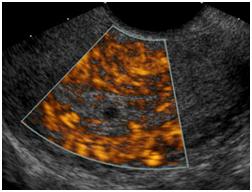

• After the uterus and ovaries are scanned through the full bladder from outside, you will be allowed to use the restroom to completely empty your bladder. You will then change into a gown and the technologist will complete the second part of the exam. A long transducer will be guided through the cervix to get visually closer and more detailed imaging of the uterus and ovaries.